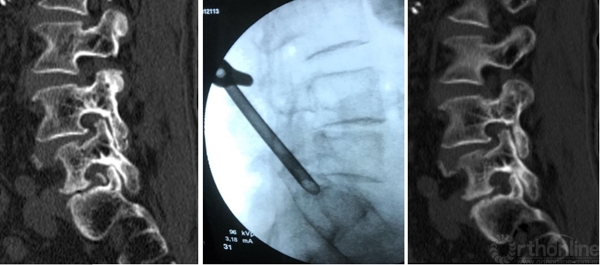

3D-CT:可观察骨性结构狭窄,如椎间孔区域狭窄,此类患者可行脊柱内镜下椎间孔扩大出口神经根减压治疗

高度脱垂病例可选择椎板开窗入路,需准备磨钻动力系统

L5/S1钙化型突出(骺环离断症),椎板间减压更加充分彻底,需配备磨钻动力系统